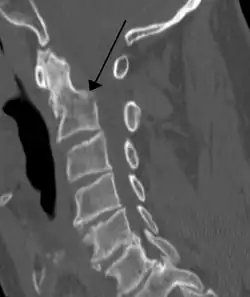

| A fracture of the base of the dens (a part of C2) as seen on CT | |